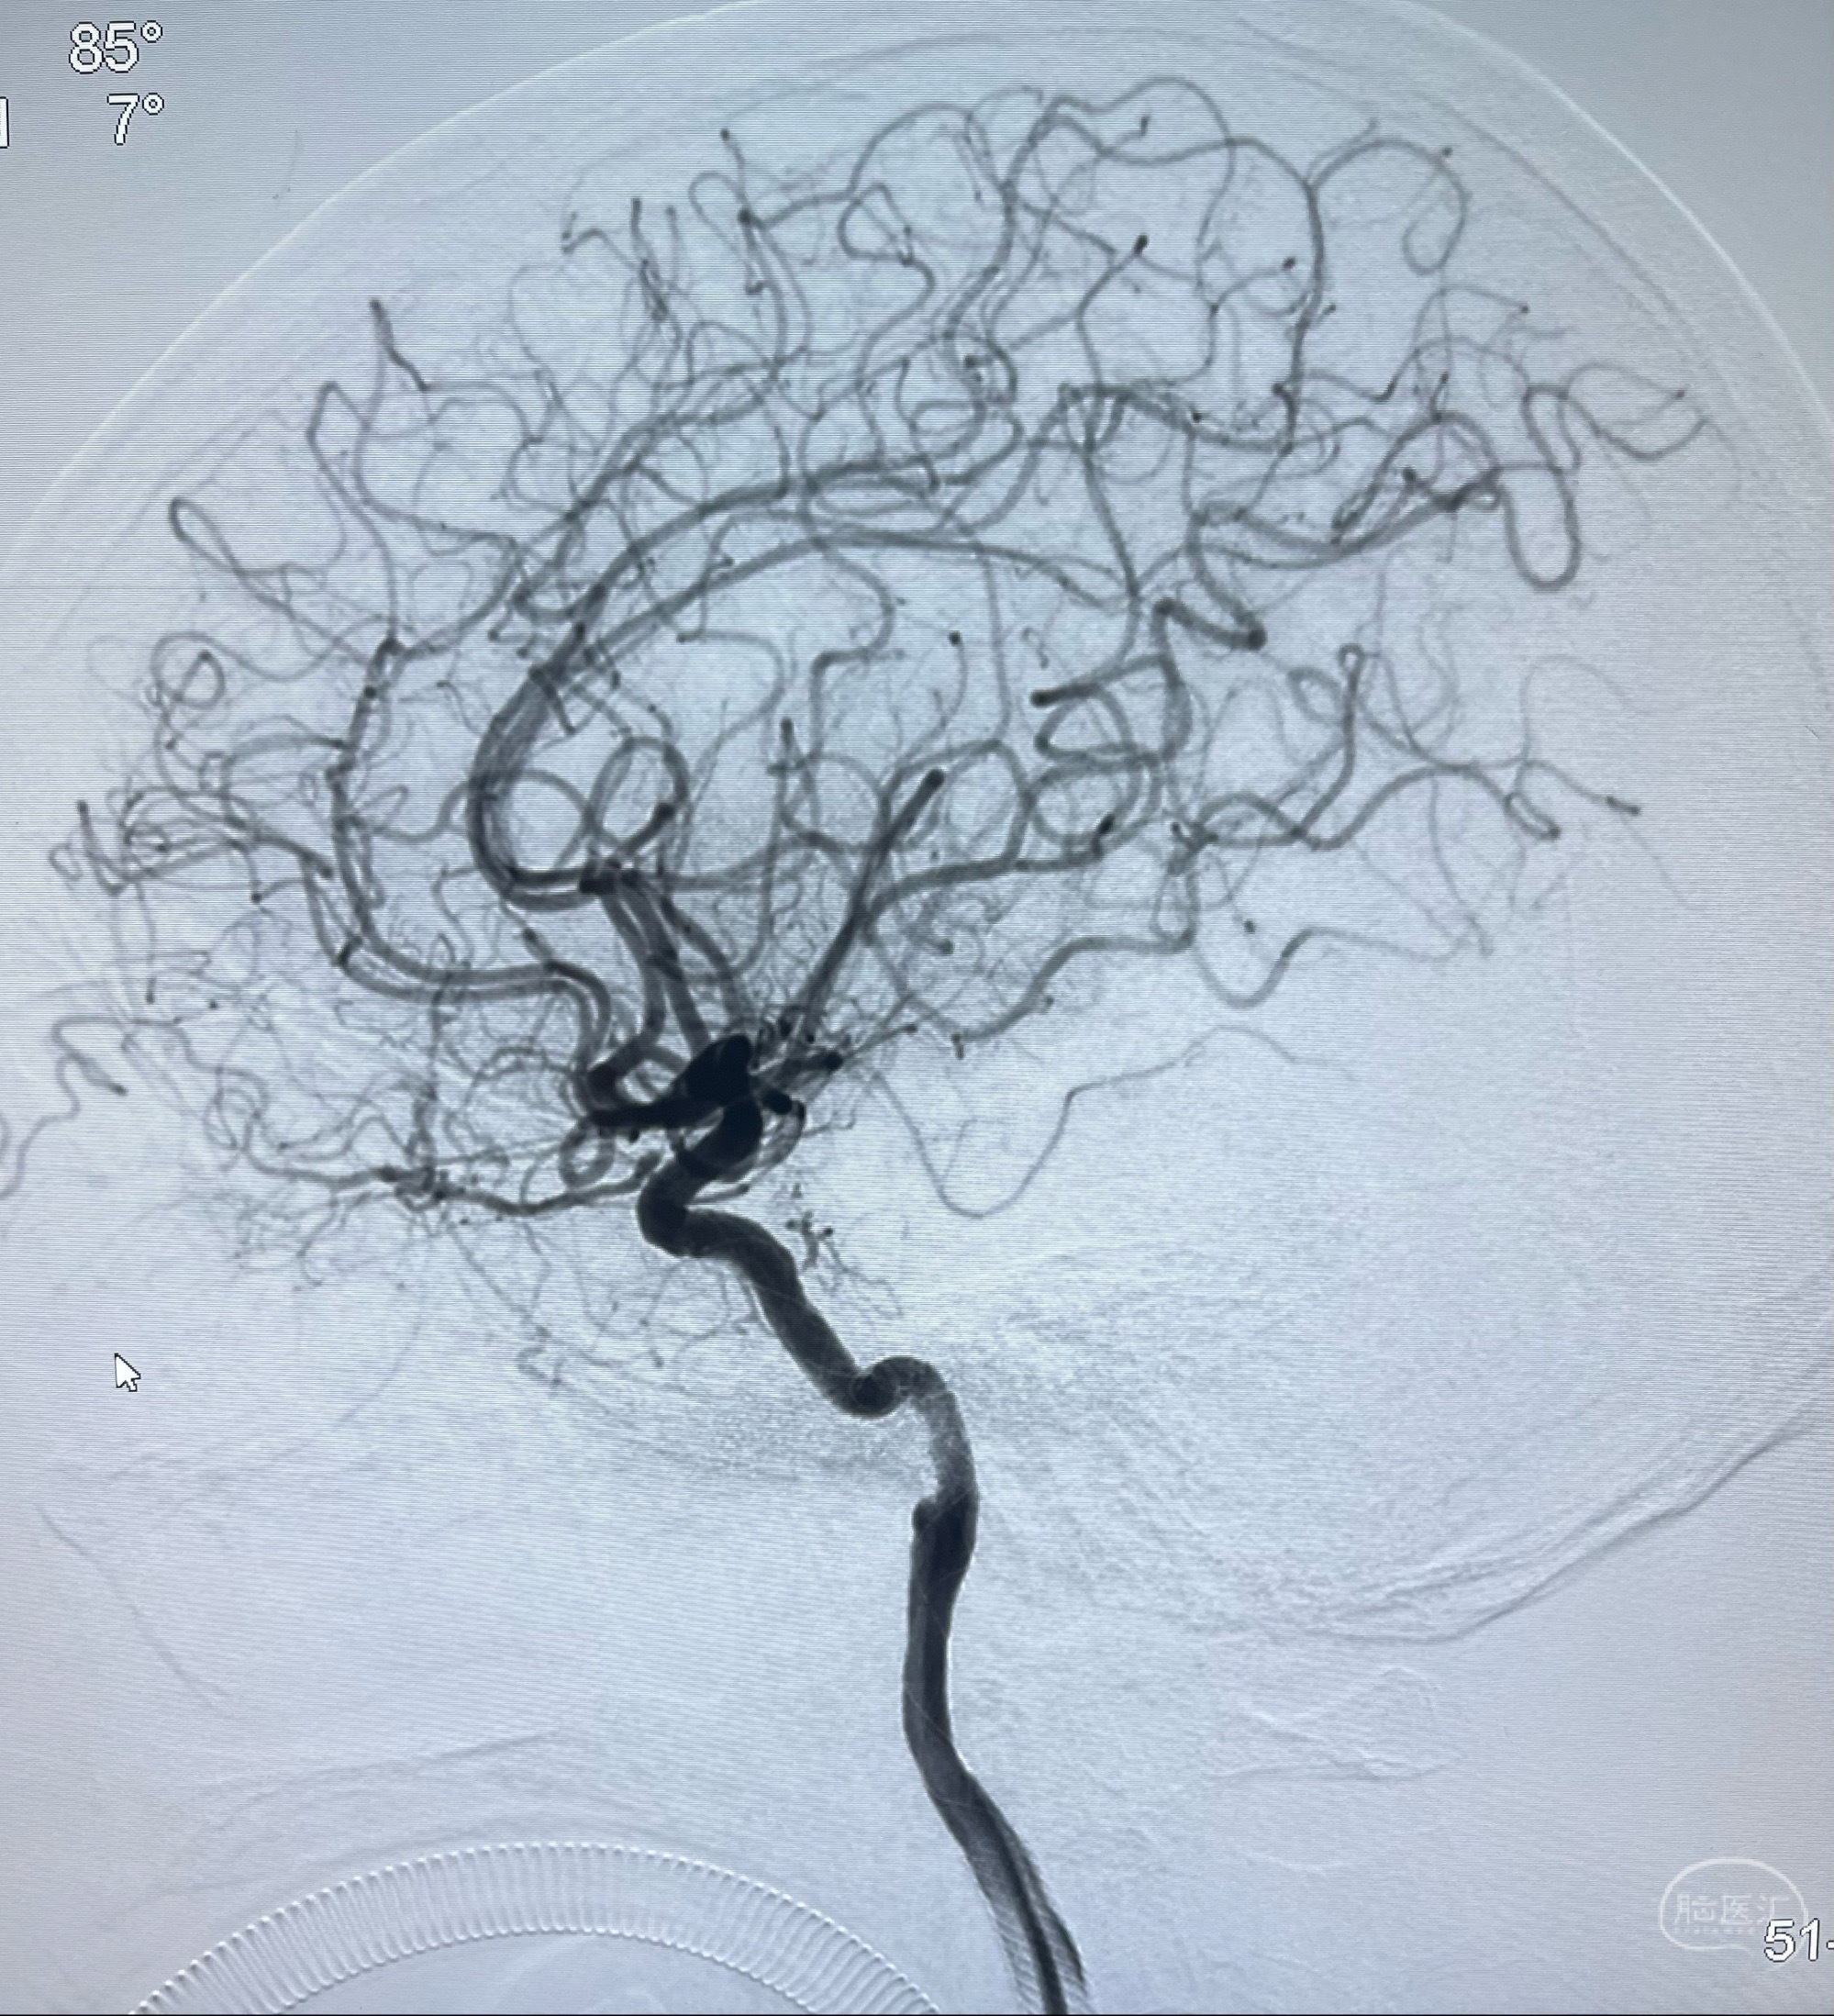

2023-07-10DSA:右侧颈内动脉岩骨段夹层伴中偏重度狭窄改变,左侧颈总动脉闭塞、右侧颈外动脉由右侧肋颈干甲颈干吻合代偿

箭头所示为颈内动脉岩骨段重度狭窄,结合MRI,考虑为肿瘤侵犯右侧颈内动脉

箭头以近至支架段管腔不规则狭窄